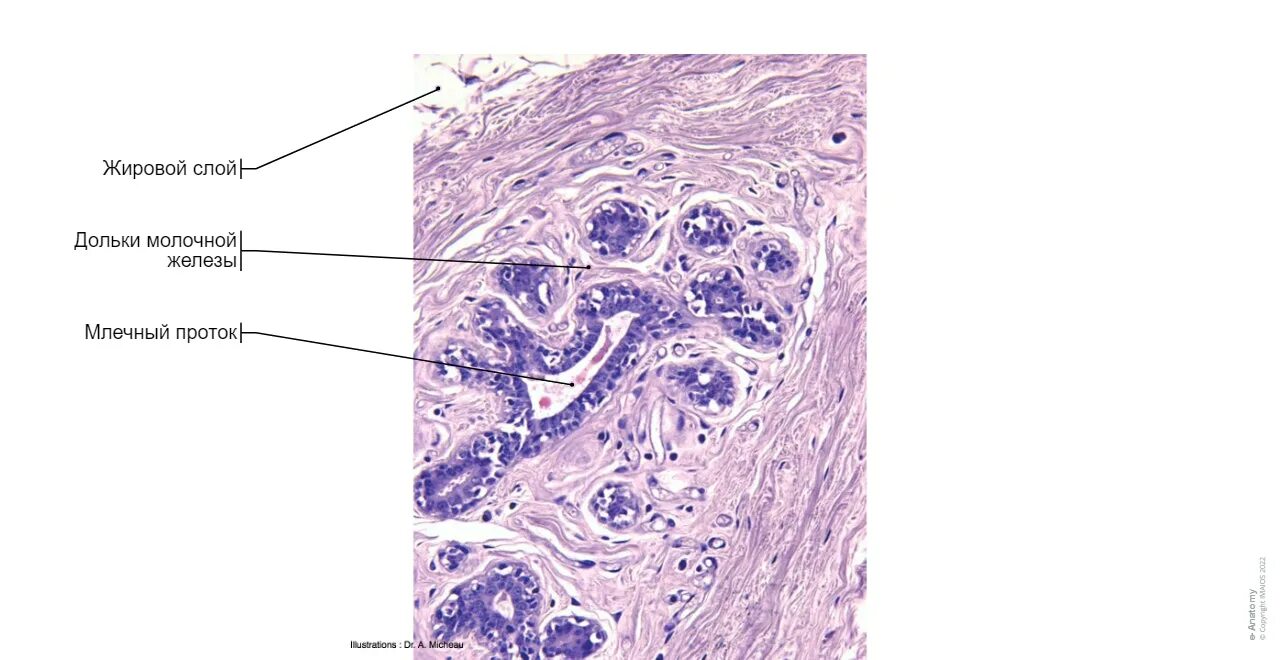

Гистология молочной железы после операции